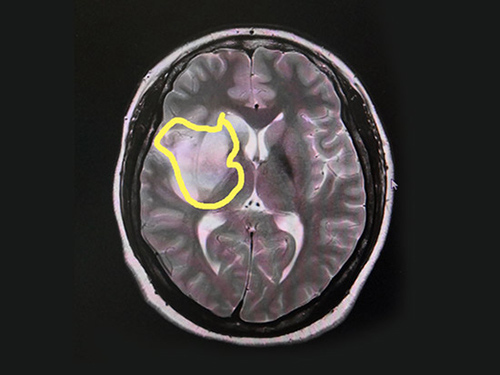

在看过患者之前做的CT影像后,有着多年临床经验的张静波主任一眼就发现了其中的端倪。张静波主任介绍,一般脑梗CT影像显示是等密度的,而该患者影像密度不均匀,有占位效应,伴有水肿,所以一般人会认为脑占位。但是影像学检查显示病灶在一条血管区域支配区,再结合患者临床,她判断为脑血管病,只是显示有占位效应。

▲患者脑梗病灶区

核磁共振MRA检查印证了她的判断。头颅MRI平扫+增强+DWI+MRA显示患者右侧大脑半球病变;MRA显示右侧颈内动脉、大脑中动脉、大脑前动脉闭塞;颈部血管彩超显示右侧颈内动脉未见血流信号,双侧颈内动脉内膜欠光滑、右侧椎动脉血流流速减低;生化检验报告显示:同型半胱氨酸血24.30μmol/L,而一般人正常含量一般为5–15 μmol/L。

综合多项检查结合患者临床,赵秋华被确诊为:右侧颈内动脉闭塞引发的急性脑梗死,并伴有高同型半胱氨酸血症。